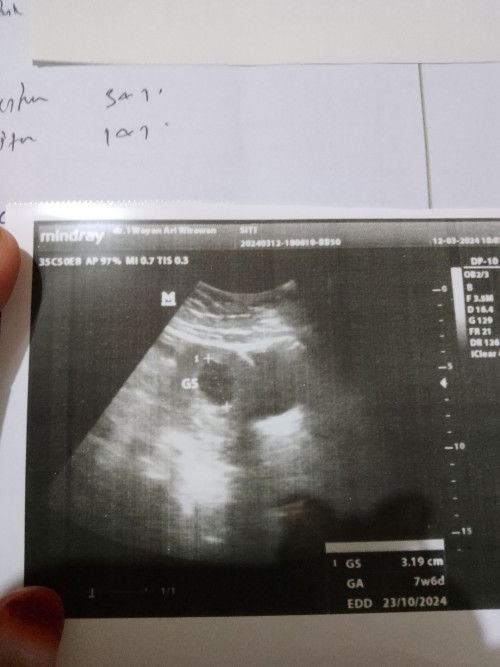

Hpht 2januari trus tdi keluar flek darah..trus aku SDH ke dokter USG Bru ada kantongnya

Bantu jawab dong bun klw ada pengalaman kaya aku..pas aku dri dokter USG baru ada kantong nya trus dibilng Bru 7 week padhl hpht aku 2 Januari Trus dokter bilng klw bulan kedepnnya ngga berkembang berarti di suruh kuret🥺😭 Takut banget Bun..ko bisa gitu sih..padhl perkiraan aku SDH 10 Minggu Ternya blm ada bakal janinnya😭